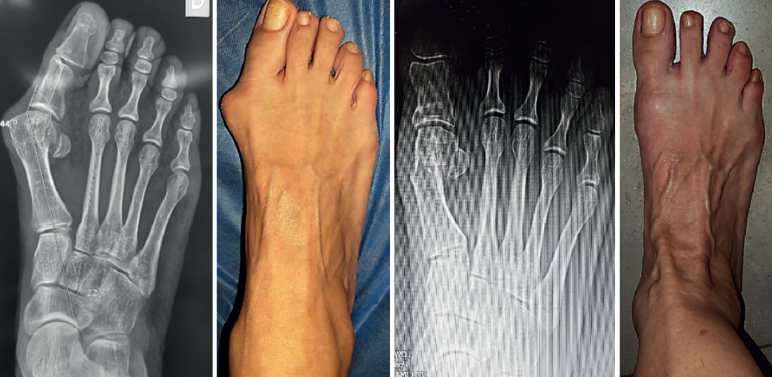

Mediante abordaje de 5 mm a nivel plantar proximal al bunion se realiza capsulotomía y exostectomía (Figuras 1A, B y C). Por otro abordaje de 3 mm realizado a 5 mm dorsal y distal del primero y a 15 o 20 mm proximal a la superficie articular (entre 7 y 10 mm del centro geométrico de la cabeza), extraarticular y equidistante a la cortical dorsal y plantar, se procede al tallado de la osteotomía de Chevron con fresa Isham larga (2,0 × 12 × 65 mm), (Figura 1D). Con la fresa dirigida, preferentemente, perpendicular al cuarto metatarsiano y llevándola ligeramente a plantar o dorsal según quisiéramos descender o elevar, respectivamente, la cabeza metatarsiana, perforamos el primer metatarsiano. En modelos sin fijación, elegimos esta dirección hacia proximal para lograr un leve acortamiento, que relaja la articulación metatarsofalángica y reduce las posibilidades de pérdida de corrección de la cabeza (Figura 2). En modelos con fijación se dirige más hacia distal, con referencia en la diáfisis del segundo metatarsiano o incluso perpendicular al primer rayo. Realizamos el corte dorsal casi vertical y el corte plantar lo más horizontal posible (paralelo al suelo), con dirección de distal a proximal, tratando de que esta rama sea más larga que la anterior. Se puede lograr de forma adicional corrección del DMAA. Una vez completa la osteotomía, se desplaza a lateral manualmente bajo visión radioscópica hasta que se logra una posición satisfactoria. No se coloca osteosíntesis. Se procede a la adición de otros gestos percutáneos de ser necesarios (liberación lateral de partes blandas, osteotomía de Akin, osteotomías de metatarsianos o dedos menores) (Figura 3).

Como vemos, la sugerencia de algún tipo de estabilización debido al riesgo de desplazamiento de la cabeza metatarsiana, menor dolor y edema es una constante en las mencionadas publicaciones. Este concepto es discutible debido a que la osteotomía de tipo Chevron realizada con la rama plantar larga y paralela al piso es intrínsecamente estable y compatible con un postoperatorio de carga precoz (Figuras 4A, B y C) al igual que las osteotomías “con fijación”(17). Los problemas relacionados con el uso de osteosíntesis en las osteotomías metatarsianas ascienden al 10-15% en diferentes series(3,9,11).